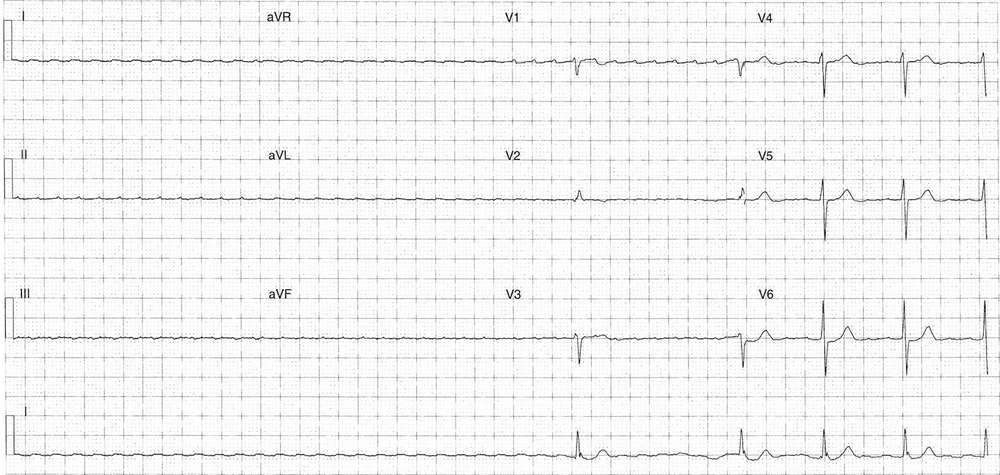

This post is an answer to the ECG Case 306

Key features

- Regular narrow complex tachycardia

- Rate ~ 130 bpm

- Left axis deviation

- Late R wave transition

- Relatively flat isoelectric line

- Possible atrial activity seen in lead III and V6

Differential diagnosis

- Atrial flutter

- Atrial tachycardia

- Accelerated junctional rhythm